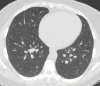

The coronavirus disease 2019 (COVID-19) pandemic is a global health care emergency. Although reverse-transcription polymerase chain reaction testing is the reference standard method to identify patients with COVID-19 infection, chest radiography and CT play a vital role in the detection and management of these patients. Prediction models for COVID-19 imaging are rapidly being developed to support medical decision making. However, inadequate availability of a diverse annotated data set has limited the performance and generalizability of existing models. To address this unmet need, the RSNA and Society of Thoracic Radiology collaborated to develop the RSNA International COVID-19 Open Radiology Database (RICORD). This database is the first multi-institutional, multinational, expert-annotated COVID-19 imaging data set. It is made freely available to the machine learning community as a research and educational resource for COVID-19 chest imaging. Pixel-level volumetric segmentation with clinical annotations was performed by thoracic radiology subspecialists for all COVID-19-positive thoracic CT scans. The labeling schema was coordinated with other international consensus panels and COVID-19 data annotation efforts, the European Society of Medical Imaging Informatics, the American College of Radiology, and the American Association of Physicists in Medicine. Study-level COVID-19 classification labels for chest radiographs were annotated by three radiologists, with majority vote adjudication by board-certified radiologists. RICORD consists of 240 thoracic CT scans and 1000 chest radiographs contributed from four international sites. It is anticipated that RICORD will ideally lead to prediction models that can demonstrate sustained performance across populations and health care systems.